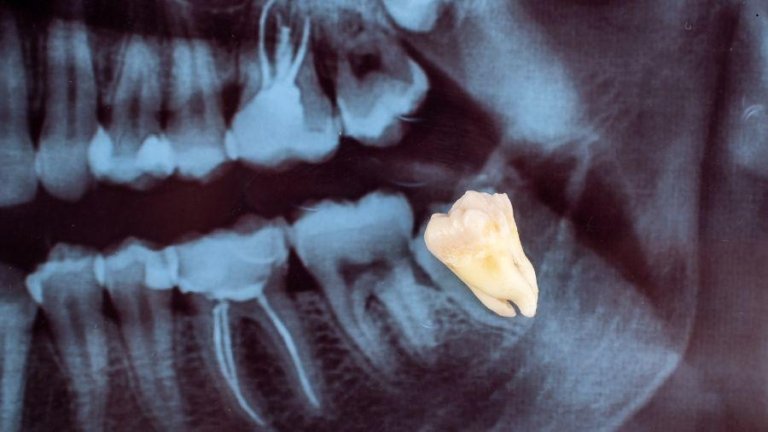

Os dentes do siso podem ser mais valiosos do que você imagina

MEDICINA REGENERATIVA

E se o dente que você arrancou pudesse salvar vidas? Para muita gente, a extração do siso é apenas o fim…